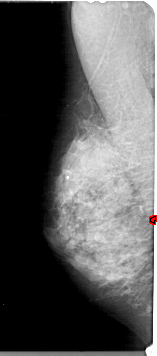

A_1926_1.LEFT_MLO

LEFT_MLO LINES 5326 PIXELS_PER_LINE 2341 BITS_PER_PIXEL 12 RESOLUTION 43.5 OVERLAY

FILE: A_1926_1.LEFT_MLO.OVERLAY

TOTAL_ABNORMALITIES 1

ABNORMALITY 1

LESION_TYPE CALCIFICATION TYPE PLEOMORPHIC DISTRIBUTION CLUSTERED

ASSESSMENT 4

SUBTLETY 2

PATHOLOGY BENIGN

TOTAL_OUTLINES 1

BOUNDARY